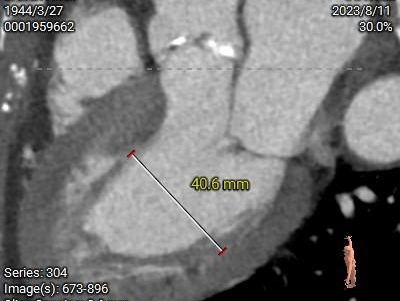

LV39.8mm

LV40.6mm